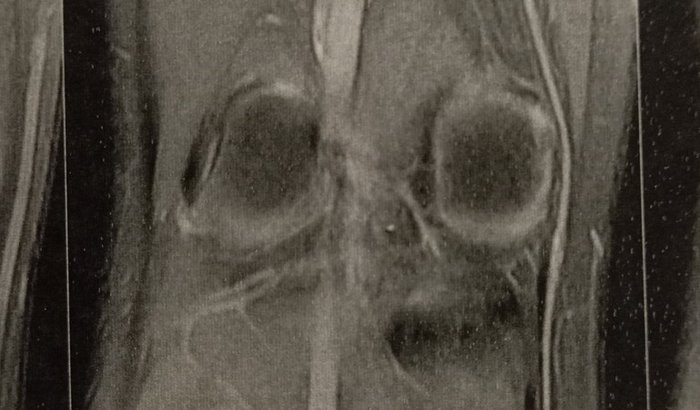

Olá, meu nome é Vittor Augusto, tenho apenas 16 anos e sou apaixonado por futsal desde pequeno.Infelizmente, durante uma partida, sofri uma lesão grave no joelho direito. Após a ressonância magnética, fui diagnosticado com ruptura total do ligamento cruzado anterior, além de outros danos que comprometem seriamente minha mobilidade.